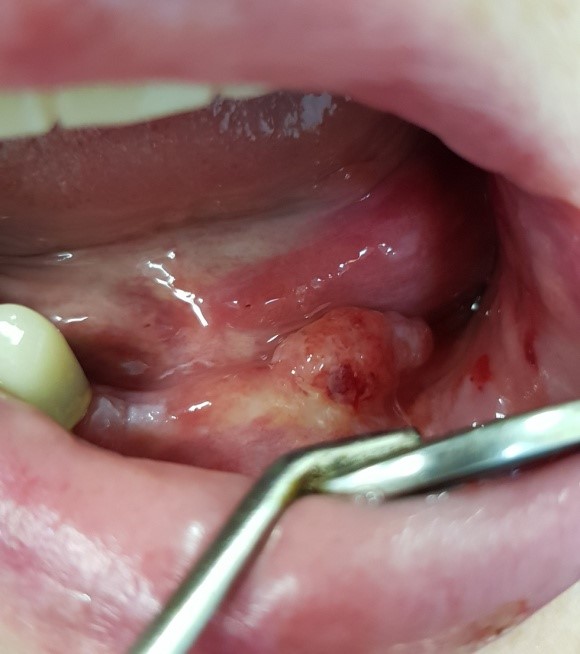

В настоящее время выявляемость рака полости рта среди нашего населения происходит на третей, четвертой стадии с локализацией на языке, подъязычной области, нижней губе и десне (фото 2, 3, 4, 5, 6)

Фото 2

Фото 3

Фото 4

Фото 5

Фото 6